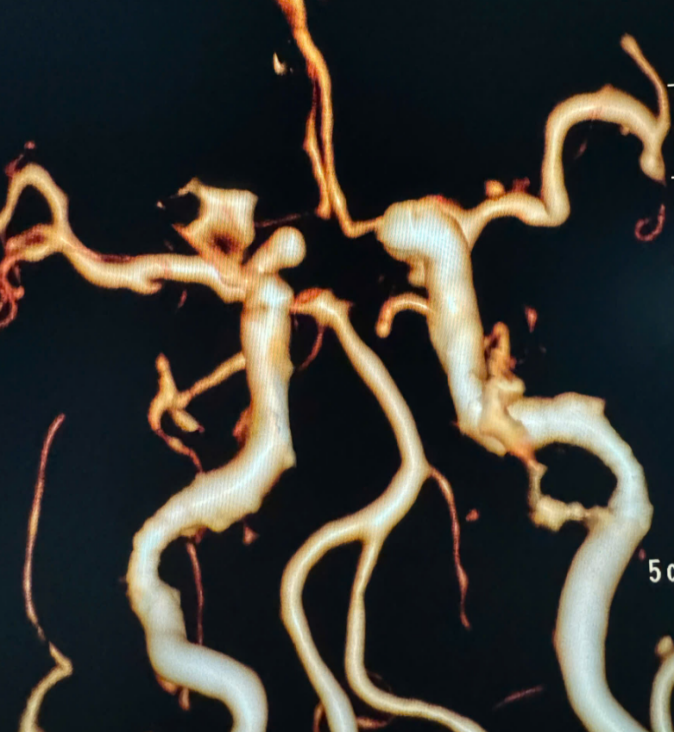

– Chụp cắt lớp vi tính mạch máu não.

– Chụp MRI/MRA.

– Chụp DSA mạch não.